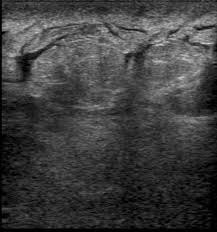

What Does Inflammatory Breast Cancer Look Like - Dermoscopy Of Inflammatory Breast Cancer Anais Brasileiros De Dermatologia : Unlike traditional forms of breast cancer, inflammatory breast cancers do not develop unusual lumps within the affected breast.. This is referred to as peau d'orange, which is french for orange skin and it is caused by cancer cells blocking the lymph vessels beneath the skin, which have formed into ridges or tiny lumps. It presents itself in a way that can be confused with a breast infection. Inflammatory breast cancer can appear normal until the tumor cells invade and block lymphatic vessels in the skin.the fluid backs up and the breast becomes discolored swell and feels hot to the touch.ibc can be confused with breast infection,but if it's cancer the antibiotic will not serve it's purpose.if you notice skin changes on your breast seek medical attention asap to distinguish breast. It does not show up on a mammogram and a breast lump is rarely present. You also may develop red, inflamed skin on the breast.

This type of breast cancer is called inflammatory because the breast often looks swollen and red, or inflamed. The texture can look like the skin of an orange. A tender area or rash on your breast often signals a common problem like an infection. It can appear bruised or puckered. But breast redness is a classic symptom of inflammatory breast cancer.

Inflammatory Breast Cancer Part 2 Breast Surgery Breast Oncology from breastsurgeryandoncology.com Mri of inflammatory breast cancer women's imaging original research. Rarely, a rash and soreness can be signs. Inflammatory breast cancer affects breast tissue and can appear unusually dimpled or thick. Inflammatory breast cancer can develop rapidly, in a few weeks to months, and can mimic a breast infection. It also may give the breast skin a thick, pitted appearance that looks a lot like an orange peel. Inflammatory breast cancer is an an aggressive and fast growing breast cancer in which cancer cells infiltrate the skin and lymph vessels of the breast. Inflammatory breast cancer is a rare and very aggressive disease in which cancer cells block lymph vessels in the skin of the breast. The texture can look like the skin of an orange.

Inflammatory breast cancer has different symptoms. It blocks the lymph vessels in the skin of your breast. It will include a red, inflamed, thickening of the breast. You also may develop red, inflamed skin on the breast. While some women went undiagnosed with breast. Inflammatory breast cancer usually starts with the reddening and swelling of the breast instead of a distinct lump. As these inflammatory breast cancer picture shows, the texture of the breast may change and appear to look dimpled or ridged, like an orange peel. Rapid onset of symptoms (redness, swelling, warmth, itching, skin thickening) are hallmarks of the disease. Mammogram imaging may show skin thickening, but often there is no distinct mass found on physical examination or … Ibc tends to grow in the form of layers or sheets of tissue, which doctors sometimes call nests. But when the lymph vessels become blocked by the breast cancer cells, symptoms begin to appear. A confirmed breast tumor usually requires treatment by surgery and may require chemotherapy, radiation, targeted biological therapy, and/or hormonal therapy. What is inflammatory breast cancer (ibc)?

Instead, the first symptoms are usually clearly visible on the breast, and they are often similar to the symptoms of relatively harmless insect bites, skin conditions, or breast infections that have no relation to cancer. Other symptoms of inflammatory breast cancer include: In other cases, it's a symptom of a common, treatable skin condition. It presents itself in a way that can be confused with a breast infection. For this reason, inflammatory breast cancer is always stage 3 or 4 at the time of diagnosis. • breast swelling, which one breast is suddenly larger than the other • breast that feels warm to touch and may look infected • itching or shooting pain Inflammatory breast cancer is a rare and very aggressive disease in which cancer cells block lymph vessels in the skin of the breast. It will include a red, inflamed, thickening of the breast. Inflammatory breast cancer occurs when cancer cells block the lymphatic vessels in skin covering the breast, causing the characteristic red, swollen appearance of the breast. It often produces no distinct tumor or lump that can be felt and isolated within the breast. It blocks the lymph vessels in the skin of your breast. This type of breast cancer is called inflammatory because the breast often looks swollen and red, or inflamed. However, this kind of cancer can develop and spread quickly (said to be aggressive).

Inflammatory Breast Cancer Symptoms And Treatment Health Com from imagesvc.meredithcorp.io Breast lesions and chest wall abnormalities 8. A confirmed breast tumor usually requires treatment by surgery and may require chemotherapy, radiation, targeted biological therapy, and/or hormonal therapy. A hallmark sign of inflammatory breast cancer is thickened skin overlying the breast. Unlike traditional forms of breast cancer, inflammatory breast cancers do not develop unusual lumps within the affected breast. But when the lymph vessels become blocked by the breast cancer cells, symptoms begin to appear. The skin looks like the skin of an orange, and may be discolored with painful and itchy breast. What is inflammatory breast cancer (ibc)? Ibc does not usually cause lumps to form in breast tissue.

This type of cancer also changes the appearance of your breasts. Rarely, a rash and soreness can be signs. It presents itself in a way that can be confused with a breast infection. Mastitis is just a breast infection that shows the same symptoms like redness and swelling, as ibc. Inflammatory breast cancer can develop rapidly, in a few weeks to months, and can mimic a breast infection. Because inflammatory breast cancer does not look like typical breast cancer it is never diagnosed in the early stages. It will include a red, inflamed, thickening of the breast. A small section may appear red, pink, or purple. It causes redness, swelling, and dimpling in the affected breast. Inflammatory breast cancer (ibc) is a rare and aggressive form of breast cancer that often appears as a rash or an irritated area of skin. It blocks the lymph vessels in the skin of your breast. Breast lesions and chest wall abnormalities 8. • breast swelling, which one breast is suddenly larger than the other • breast that feels warm to touch and may look infected • itching or shooting pain